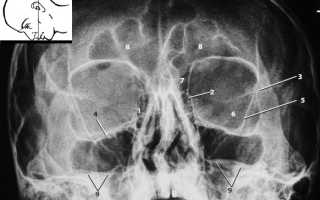

В МНИИГБ им. Гельмгольца методика Комберга-Балтина применяется в модифицированном виде (Л. Я. Ициксон): прямой снимок орбиты выполняют в задней проекции.

Методика исследования глазниц в задней прямой проекции

- Больной лежит на спине, слегка приподняв подбородок.

- Голову больного укладывают так, чтобы исследуемая глазница соответствовала центру кассеты, а сагиттальная плоскость глазницы была бы строго перпендикулярна плоскости кассеты и параллельна ее сагиттально направленным краям.

Для этого можно воспользоваться простым приемом, сущность которого заключается в следующем: врач мысленно соединяет линией наружные углы глазных щелей больного, и эта линия должна быть параллельна соответствующему краю кассеты. - Взор исследуемого глаза должен быть направлен перпендикулярно кассете.